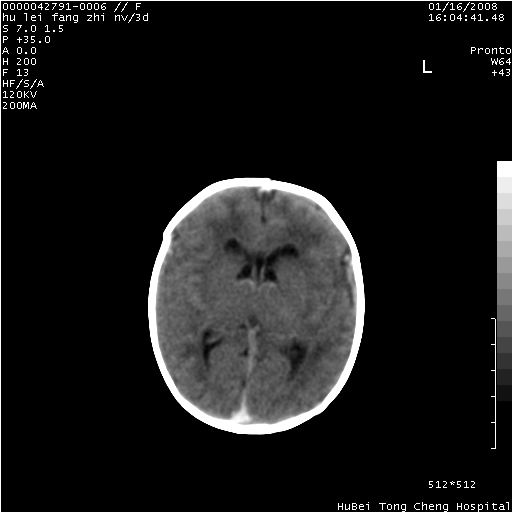

患儿 女,3天。惊跳,纳差。第二胎顺产,羊水ⅱ度。

临床诊断:hie?

颅脑ct轴位平扫(层厚、层距均为7mm),图像如下:

hie合并蛛网膜下腔出血

hie合并蛛网膜下腔出血,五、六脑室形成。

支持hie伴少量蛛血.